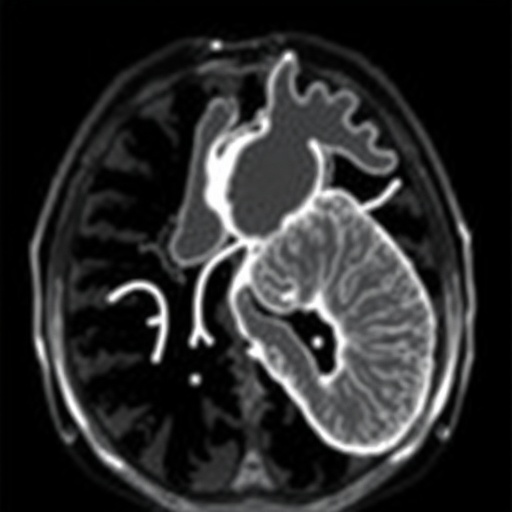

Magnetic resonance imaging has rapidly evolved as a vital tool in pediatric cardiology, not only for its ability to provide detailed anatomical images but also for its utility in assessing cardiac function and tissue characterization. The non-invasive nature of MRI makes it particularly suited for use in children, who may have difficulty tolerating other forms of testing. This technique helps in differentiating between various types of cardiomyopathies and can provide critical information regarding myocardial inflammation, fibrosis, and perfusion.

One of the notable advancements discussed in the update is the integration of advanced MRI sequences such as T1 and T2 mapping, which allow for a more nuanced evaluation of myocardial tissue properties. These sequences have shown promise in diagnosing specific cardiomyopathies, including hypertrophic and dilated variants, by highlighting underlying pathologies that may be missed by traditional imaging methods. This reflects a broader shift towards using MRI not just as a tool for anatomical visualization, but as a means of obtaining vital physiological information that informs therapeutic decisions.

In addition to genetic insights, the update touches upon the role of other imaging modalities and how they complement MRI findings. For instance, echocardiography remains an essential initial diagnostic tool, particularly for assessing ventricular function and anatomy. However, the added detail provided by MRI allows for a comprehensive evaluation that can significantly enhance the understanding of a child’s cardiac condition.